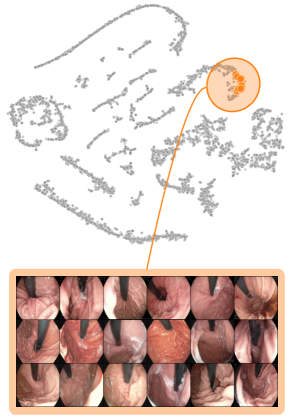

Both input and latent relevance clustering require subsequent human supervision to determine whether outlier clusters represent valid or spurious behavior. To semi-automate this process, Anders et al. [3] propose using Fisher Discriminant Analysis [37] to rank class-wise clusterings by linear separability, while Dreyer et al. [27] computes similarities between prototypes. The results of clustering approaches can serve as an initial set for bias modeling methods outlined in Sec. 3.2, which can be refined iteratively. An example outlier cluster of latent relevances is shown in Fig. 4 (top), with all samples containing the spurious band-aid concept.

4.2 Model Perspective – Detecting Spurious Representations

In contrast to detecting spurious samples, recent work focuses on identifying spurious model internals directly. This aligns with mechanistic interpretability, which seeks to decipher the internal mechanics of DNNs [56, 31, 13]. As outlined in Sec. 3.1, various global XAIs methods aim to explain the role of individual neurons, and these insights can be leveraged to detect spurious model internals by clustering learned concepts and identifying outliers. Given input data with samples, Pahde et al. [59] compute spatially aggregated relevances . Subsequently, they compute the pairwise cosine distance per column (i.e., channel/concept) and embed the resulting distance matrix in a low-dimensional space using dimension reduction techniques like t-Distributed Stochastic Neighbor Embedding (t-SNE) [71] or Uniform Manifold Approximation and Projection (UMAP) [49]. This low-dimensional embedding can be visualized to identify outliers through human inspection or anomaly detection algorithms, such as the Local Outlier Factor [12]. In summary, outlier representations can be identified in an embedding representation , obtained as

where reduces the dimension to , and the pairwise distance function is applied along all channel dimensions in the latent representation , either given by activations or relevance scores for layer . Note that this approach assumes over-parameterization resulting in redundant neurons, allowing to distinguish between similar and dissimilar concept representations. An example is shown in Fig. 4 (bottom), where latent relevance scores from a ResNet50 model trained for melanoma detection are used to identify outlier concepts, specifically a cluster focusing on band-aids rather than clinically relevant features. Notably, Eq. 3 can easily be extended to find outlier directions instead of neurons. Specifically, this involves a linear transformation of latent representations using the directions of interest, e.g., obtained in unsupervised manner as described in Sec. 3.1.

Data Perspective

We first apply SpRAy in input and latent space, computing input feature importance scores using LRP summed over color channels. To obtain latent relevances, we use intermediate relevance scores in the LRP computation process after the (out of four) residual block, max-pooling over spatial dimensions to yield relevance scores for layer with channels. The clustering of pairwise cosine distances between heatmaps is shown in Fig. 6 (top left). Detected outlier clusters contain samples with spatially coherent biases, e.g., the black circle around the lesions originating from microscopes (). In contrast, clustering latent relevance scores reveals more complex, less spatially dependent clusters, as shown in Fig. 6 (top right), including the ruler artifact () and the microscope (). Compared to those in input space, the cluster for the microscope in latent space represents a more diverse high-level concept. In the input space visualization, we further highlight samples from the ruler cluster detected in latent space. Instead of forming a cluster, they spread across the entire embedding space, indicating that the bias is too complex to be detected in input space.